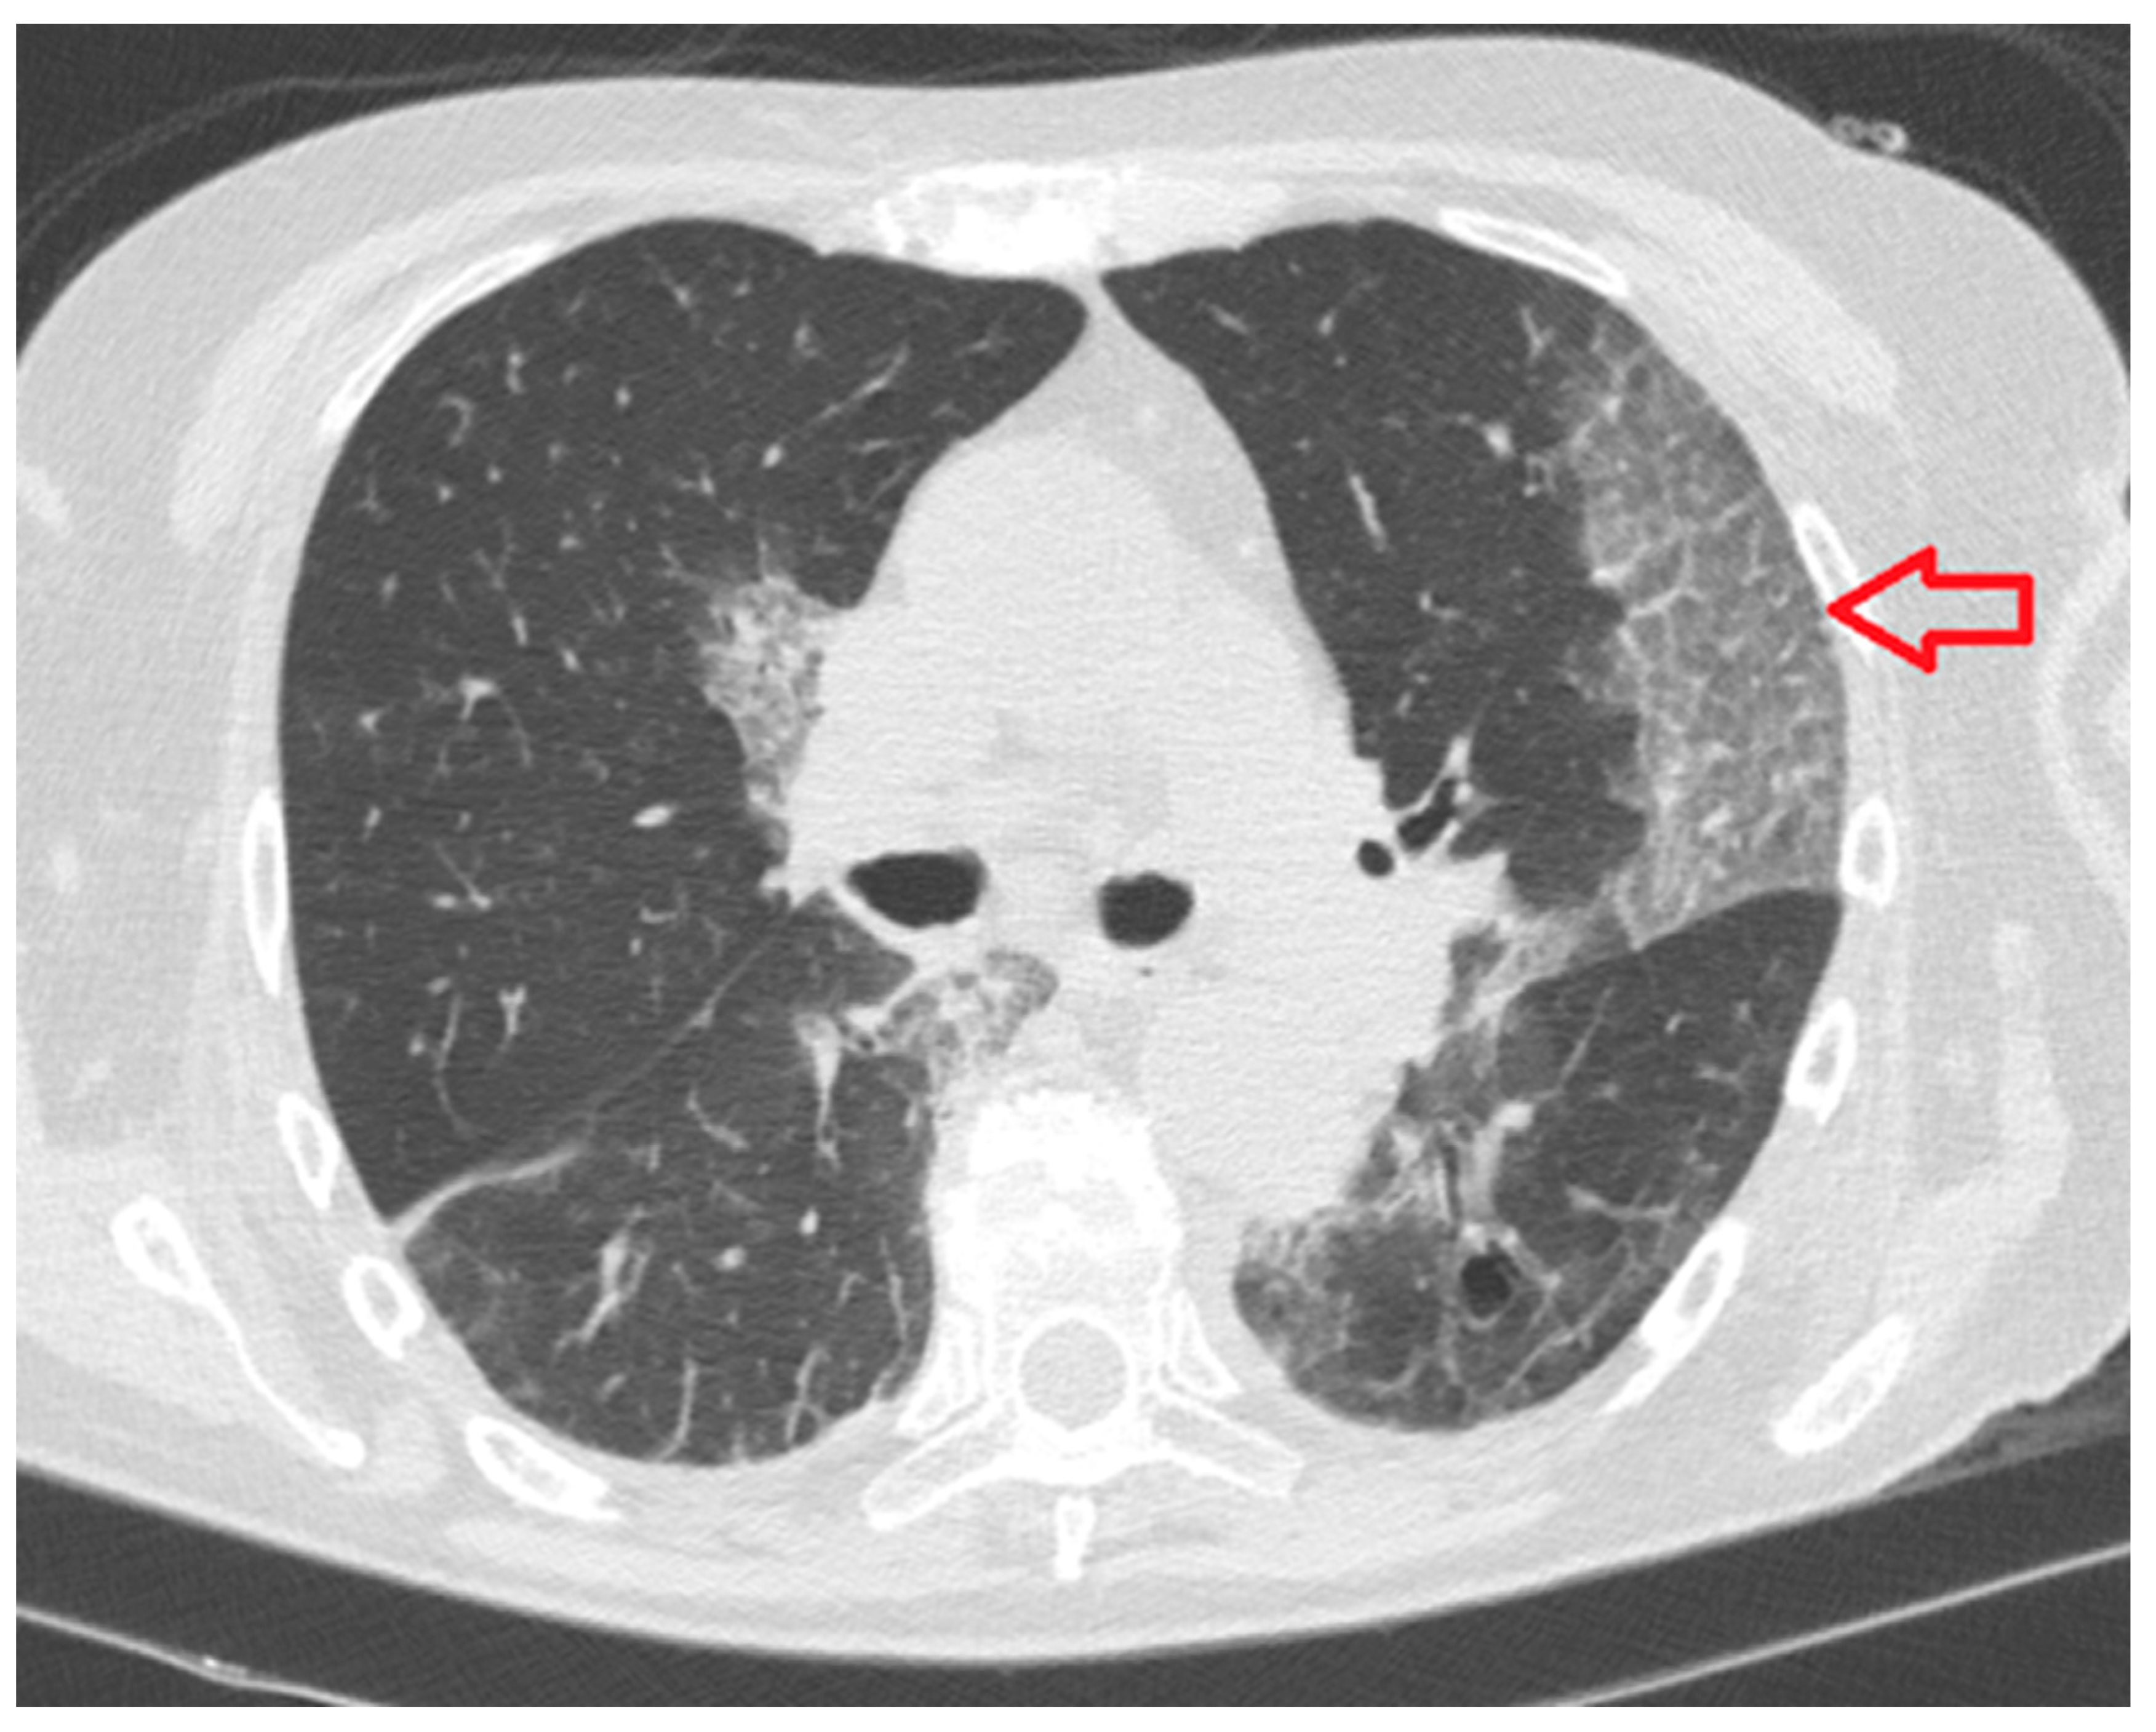

- Consolidation: homogeneous increase in lung parenchymal opacity obscuring the vascular margins and airway walls with an air bronchogram (pattern of air-filled bronchi on a background of opaque airless lung) (Figure 3);